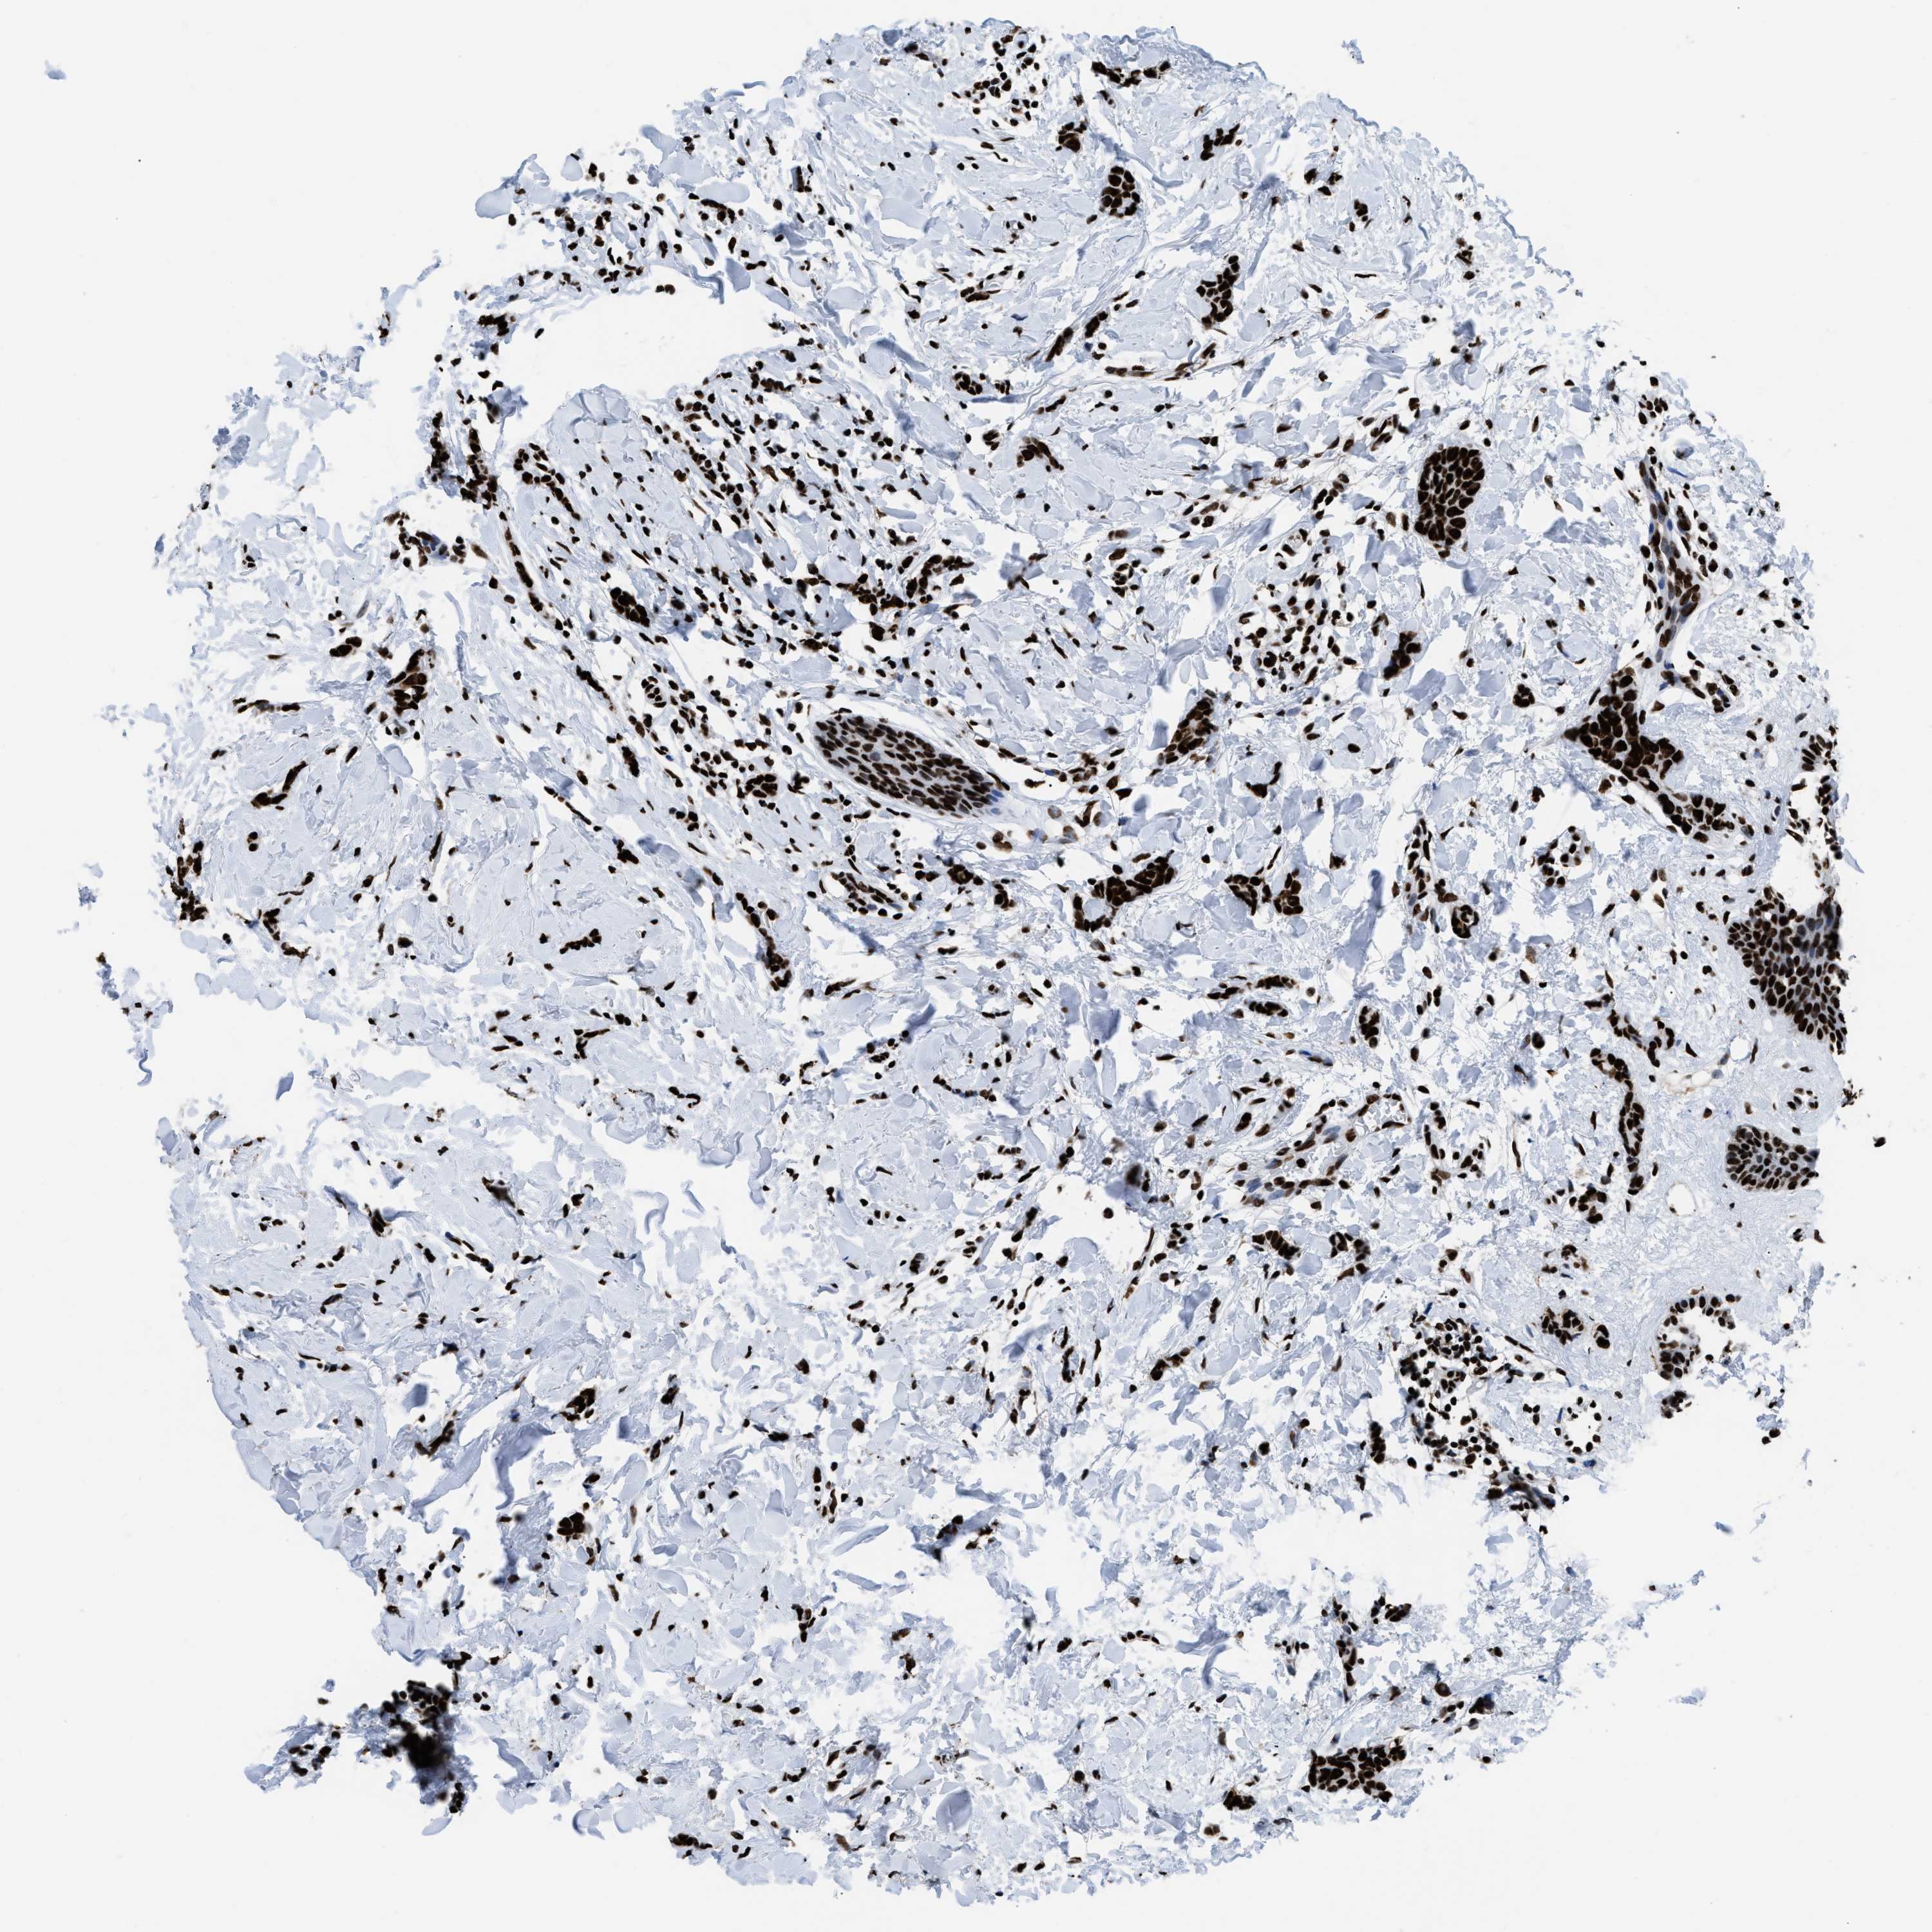

CANCER BREAST CANCER Show tissue menu

Breast cancer

Human cancer